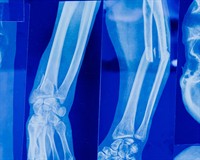

Найчастіше рентгенографію роблять, якщо є підозра на перелом кісток.

Суть дослідження в тому, що рентгенівські промені проходять через тканити тіла. Кістки на плівці матимуть білий колір. Якщо кістка пошкоджена (тріщина чи перелом) на знімку буде помітно "розрив" у білому забарвлені кістки.